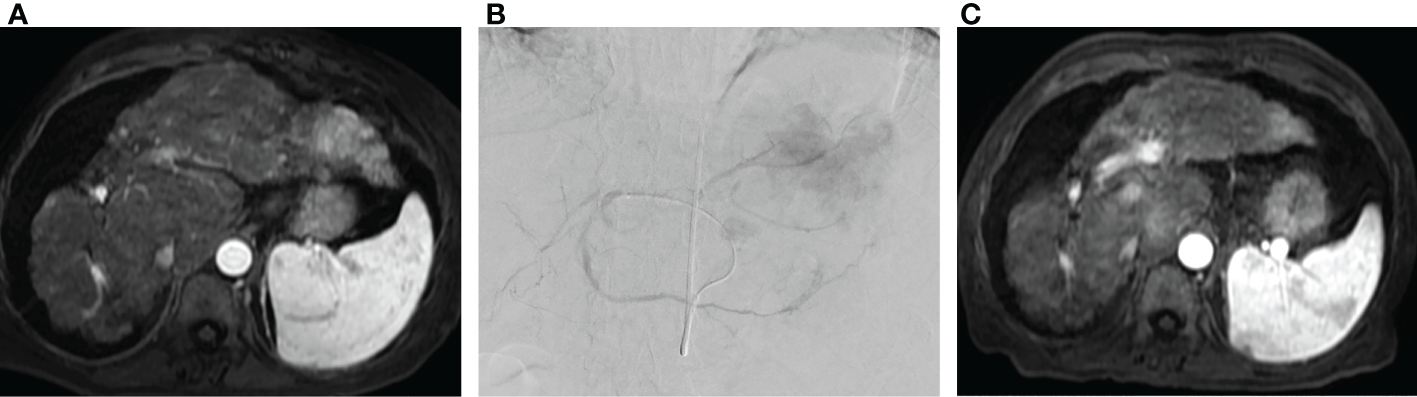

Figure 3

Radioembolization as salvage therapy. (A) Pre-procedure MRI in patient with metastatic colorectal cancer to the liver following three lines of chemotherapy demonstrating multifocal metastatic disease involving the left hepatic lobe. (B) Transradial radioembolization of the left hepatic lobe with Yttrium-90 resin microspheres via a replaced left hepatic artery arising from a left gastric artery. (C) Post procedure MRI with interval reduction in size and enhancement of left hepatic lobe tumor.